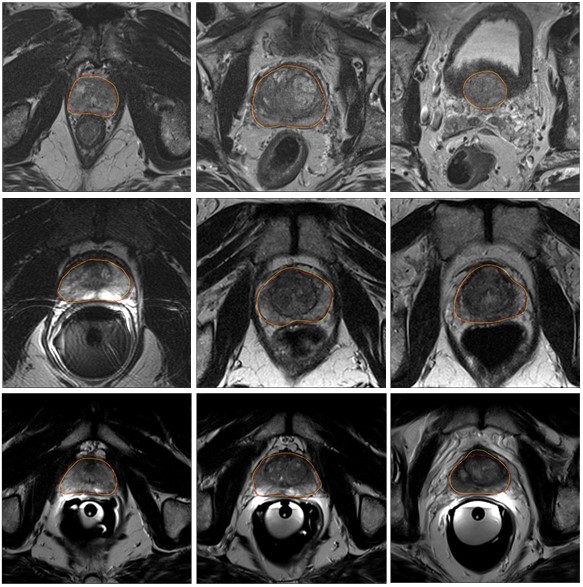

图二:部分分割结果。黄色轮廓线为专家标记结果,红色轮廓线为我们所提方法分割结果。